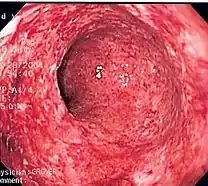

- Ulcerative inflammation: Inflammation occurring near an epithelium can result in the necrotic loss of tissue from the surface, exposing lower layers. The subsequent excavation in the epithelium is known as an ulcer.